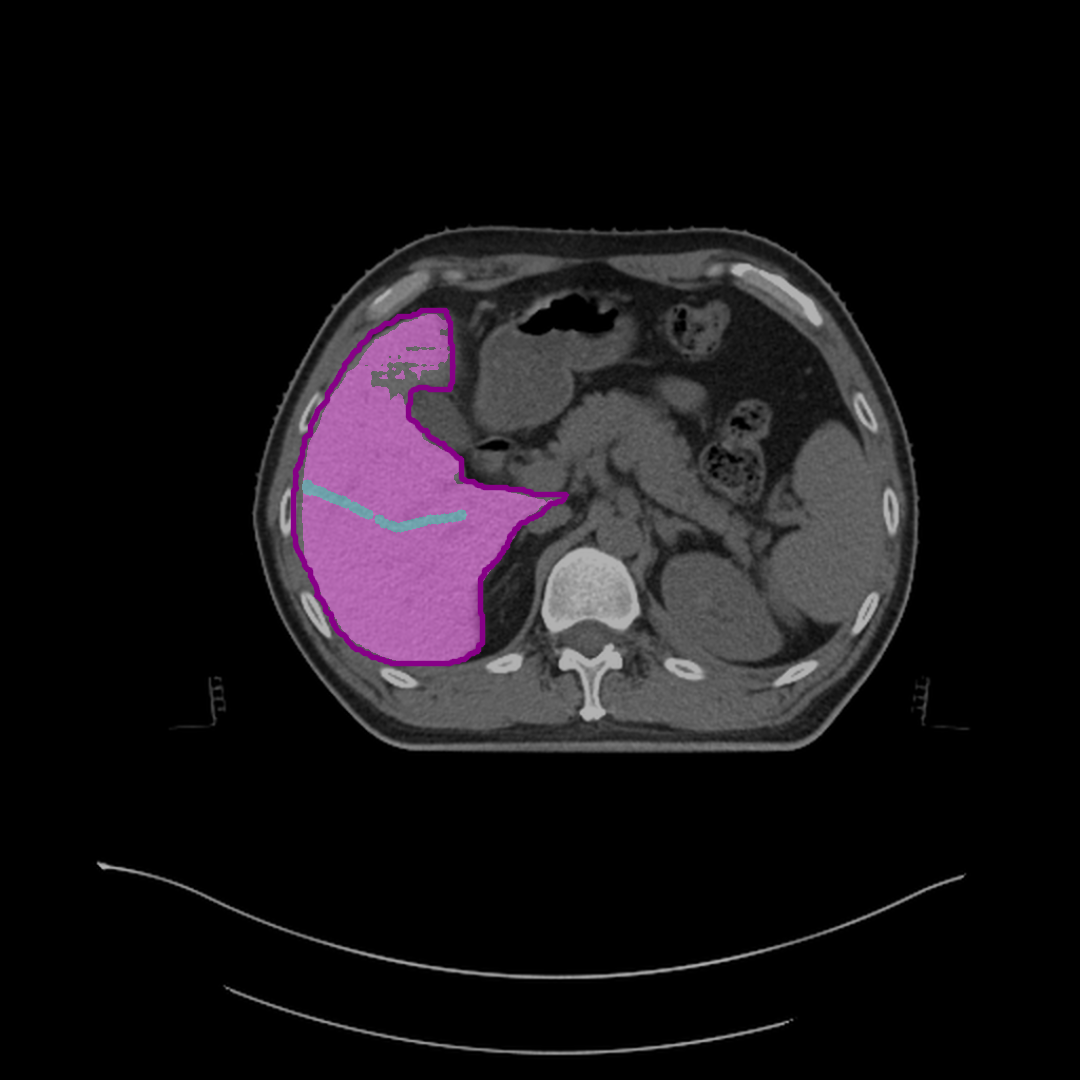

Refer to caption

(b) Mask after half correction.

(c) Mask after full correction.

Figure 4: Steps to correct segmentation masks for various abdominal organs, such as the spleen, left kidney, and liver, on different CT slices. Each subfigure shows the outline of reference segmentation contours, the predicted segmentation mask, and gaze points (blue) used for predictions based on gaze.